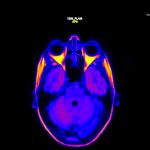

“Ajuruum” käsitleb migreeni kogemuse tajuelamusi läbi visuaalide ja heli. Installatsiooni algpunktiks on kunstniku isiklik kogemus migreeniga. Impulsi teose loomiseks andis soov tõsta teadlikkust migreeni kui haiguse olemusest. Peale mitmeid MRT uuringuid sündis antud materjalist videoteos ning sellest kasvas välja ka installatiivne ja heliline osa. Heli ja pilt sai valitud just seetõttu, et enamikel migreenide all kannatajatel tekib lisaks muudele sümptomitele enne hoogu ja/või hoo ajal ülitundlikkus valguse ja helide suhtes. Tihti nägemine kas kaob osaliselt või tekib objektide ümber aura. Erinevate helide kuulmine tekitab teravaid valuaistinguid nii peas kui kehas. Diagnoosi saanud inimesed toovad välja, et ühed hullemad helid on just kellatiksumine, söögiriistade omavaheline põrkumine, ukse avamine ja sulgemine ning telefoni poolt tekitatud helid. Sellest kogemusest annab aimu mürasümfoonia, mida on võimalik juuresolevatest kõrvaklappidest kuulata.